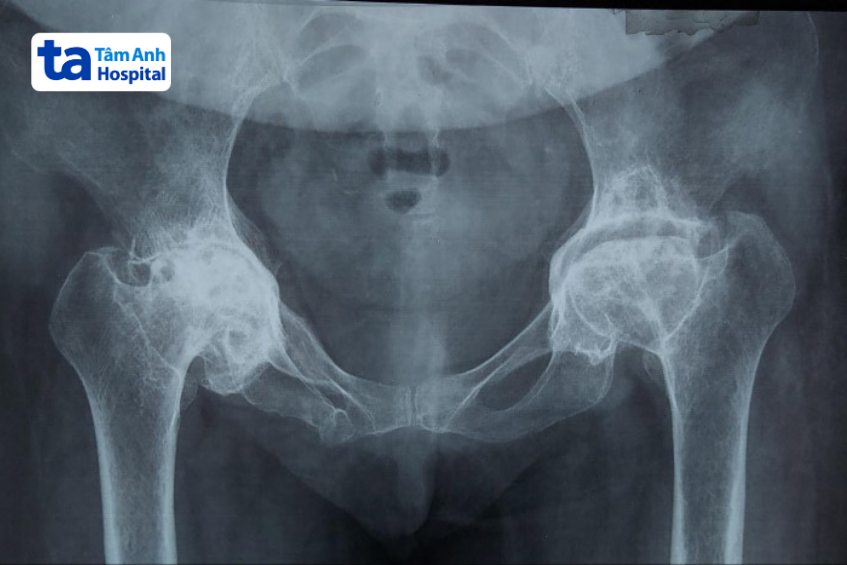

Hình ảnh viêm khớp háng trên X-quang có thể giúp bác sĩ đánh giá tình trạng và giai đoạn tiến triển của bệnh. Viêm khớp háng bao gồm 4 cấp độ tiến triển dựa vào mức độ tổn thương ở khớp háng: (1)

Chụp X-quang có thể được xem là phương pháp chẩn đoán hình ảnh viêm khớp háng đơn giản nhất và có chi phí rẻ nhất. Thông qua kết quả chụp phim X-quang, bác sĩ có thể quan sát được cấu trúc xương và tình trạng chấn thương ở các mô mềm xung quanh (nếu có). Trên phim X-quang không thể thấy được tình trạng sụn khớp, nhưng bác sĩ có thể chẩn đoán viêm khớp háng gián tiếp thông qua khoảng cách giữa xương đùi và ổ cối xương chậu.